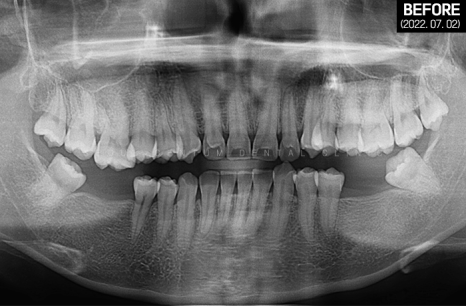

그래서 우선 파노라마 엑스레이 촬영으로

전체적인 구강 환경을 살펴봤는데요.

전치부는 과잉 밀집으로 몰려있는 것이 보였고

위턱은 사랑니까지 맹출 되어

아주 빽빽한 치열을 갖고 계셨습니다.

아래턱은 어금니 상실 부위가 여러 군데여서

식사가 불편하셨을 것으로 예상되었습니다.